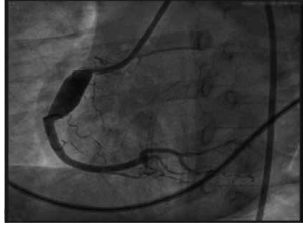

Considere a imagem a seguir.

(Arquivo pessoal; imagens usadas com autorização)

Essa é uma angiocoronariografia realizada por um paciente. Assinale a alternativa que indica, corretamente, qual é o diagnóstico etiológico e qual é o tratamento que deveria ser instituído na suspeita diagnóstica.